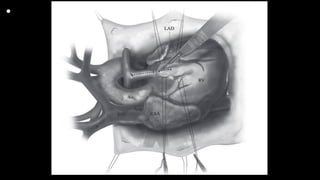

• Figure 1 After median sternotomy or partial lower sternotomy, a

pericardial well is established. The heart is inspected from the outside, and

typically there is a large size discrepancy between the ascending aorta and

the main pulmonary artery (PA), as well as occasionally a “dimple”

seen on the RVOT. The location of the coronaries is noted, knowing that in

TOF, the right coronary artery origin is rotated leftward and is

usually close to the MPA. The edges of the infundibulum are marked with

4-0 silk mattress stay sutures. The LAD denotes the septum, and

the lateral stay sutures are placed several millimeters away from the LAD.

A fine polypropylene suture is place to mark the exact middle of

the PA bifurcation, for future orientation when making the main PA

incision. A patent ductus arteriosus, if present, is ligated or clipped.

SVC = superior vena cava; Ao = aorta; RAA = right atrial appendage; LAD =

left anterior descending; RV = right ventricle.